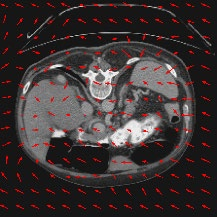

Transformers have made remarkable progress towards modeling long-range dependencies within the medical image analysis domain. However, current transformer-based models suffer from several disadvantages: (1) existing methods fail to capture the important features of the images due to the naive tokenization scheme; (2) the models suffer from information loss because they only consider single-scale feature representations; and (3) the segmentation label maps generated by the models are not accurate enough without considering rich semantic contexts and anatomical textures. In this work, we present CASTformer, a novel type of generative adversarial transformers, for 2D medical image segmentation. First, we take advantage of the pyramid structure to construct multi-scale representations and handle multi-scale variations. We then design a novel class-aware transformer module to better learn the discriminative regions of objects with semantic structures. Lastly, we utilize an adversarial training strategy that boosts segmentation accuracy and correspondingly allows a transformer-based discriminator to capture high-level semantically correlated contents and low-level anatomical features. Our experiments demonstrate that CASTformer dramatically outperforms previous state-of-the-art transformer-based approaches on three benchmarks, obtaining 2.54%-5.88% absolute improvements in Dice over previous models. Further qualitative experiments provide a more detailed picture of the model's inner workings, shed light on the challenges in improved transparency, and demonstrate that transfer learning can greatly improve performance and reduce the size of medical image datasets in training, making CASTformer a strong starting point for downstream medical image analysis tasks.